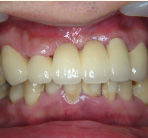

セラミック治療

こんな歯並びでもご心配なく。矯正という方法をとらなくても、ここまできれいに治せるんです。見た目だけでなく歯ブラシもやり易くなりました。笑顔に自信がつきますよ。

- 施術前

- 施術後